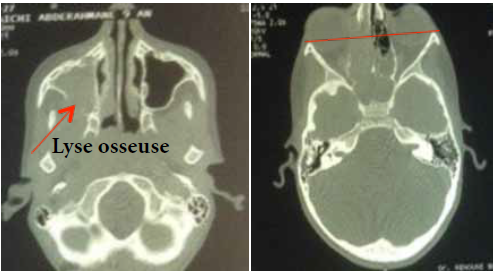

Examens complémentaires :

L’angiographie à la Fluorescéine

L’angiographie à la fluorescéine est un examen capital car elle permet de faire le bilan de l’atteinte rétinienne, et de retrouver des anomalies infra cliniques dans 6% des cas à type de vascularites rétiniennes (figure 4).

Par ailleurs l’angiographie peut objectiver, un œdème maculaire (figure 5)

La Tomographie en Cohérence Optique (OCT) L’OCT est indiquée essentiellement dans l’œdème maculaire compliquant les atteintes du segment postérieur (figure 6). Elle permet de mesurer de manière reproductible l’épaisseur maculaire, afin de suivre l’évolution de cet œdème et donc d’adapter les différents traitements (4.5).